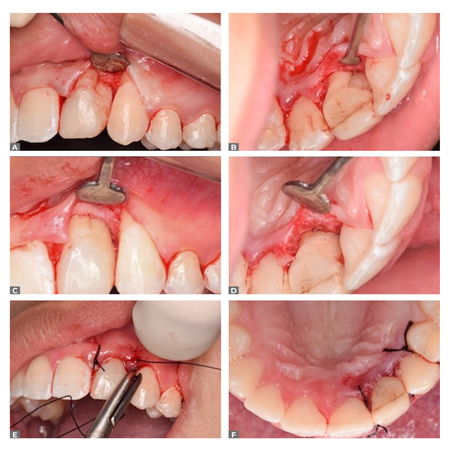

INTRODUCTION: External inflammatory resorption presents a challenging diagnosis for identification of the extent and nature of the process, especially when the resorption defect is located on the buccal or palatal surfaces. OBJECTIVE: To describe the diagnosis and treatment of a patient with external inflammatory resorption in a permanent tooth associated with advanced periodontitis. CASE REPORT: The patient presented periodontitis with extensive bone loss in the lower anterior teeth and an...

INTRODUÇÃO: Uma reabsorção externa inflamatória apresenta diagnóstico desafiador na identificação da sua extensão e na natureza do processo, especialmente quando o defeito de reabsorção se encontra nas faces vestibular ou palatina. OBJETIVO: Descrever o diagnóstico e tratamento de um paciente com uma reabsorção externa inflamatória em dente permanente associado a um quadro de periodontite avançada. RELATO DE CASO: Paciente apresentando periodontite com extensa perda óssea...